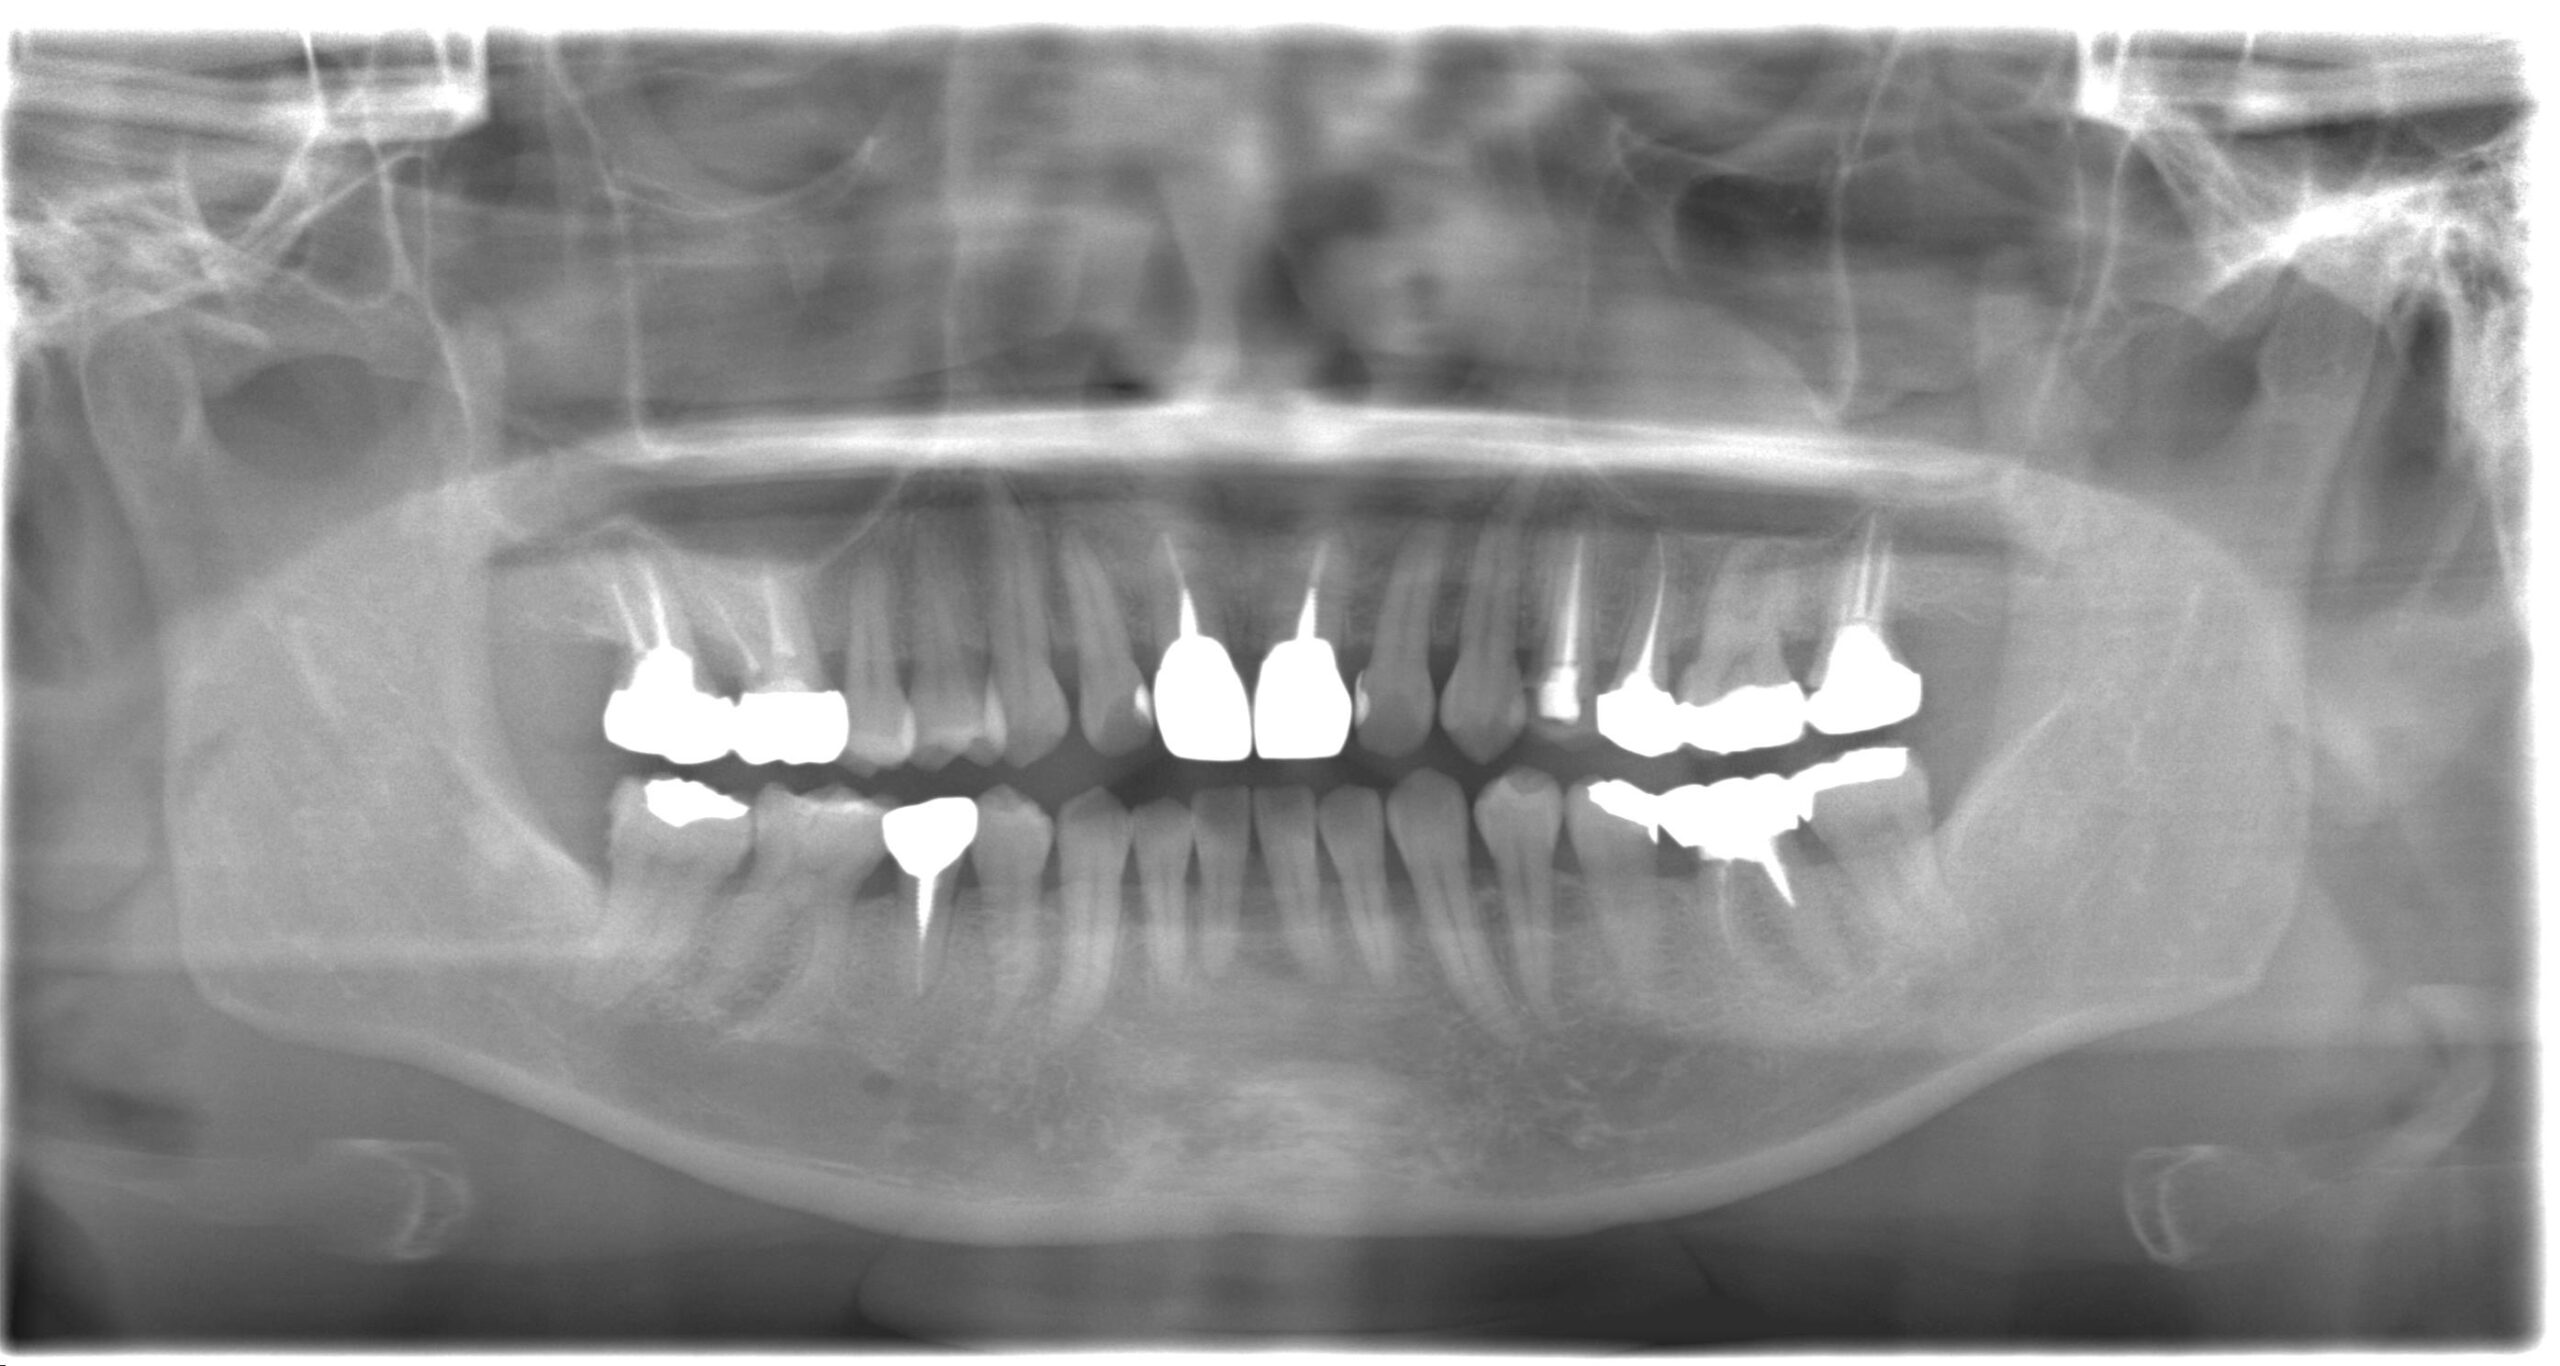

レントゲン、口腔内写真

セラミック治療を進めていく際には、患者様の目指しているゴールを明確にして、あとは根のコンディションがどうなのか?歯茎のコンディションはどうなのか?を考慮して、最終的なゴールを決めていきます。

- パノラマレントゲン撮影